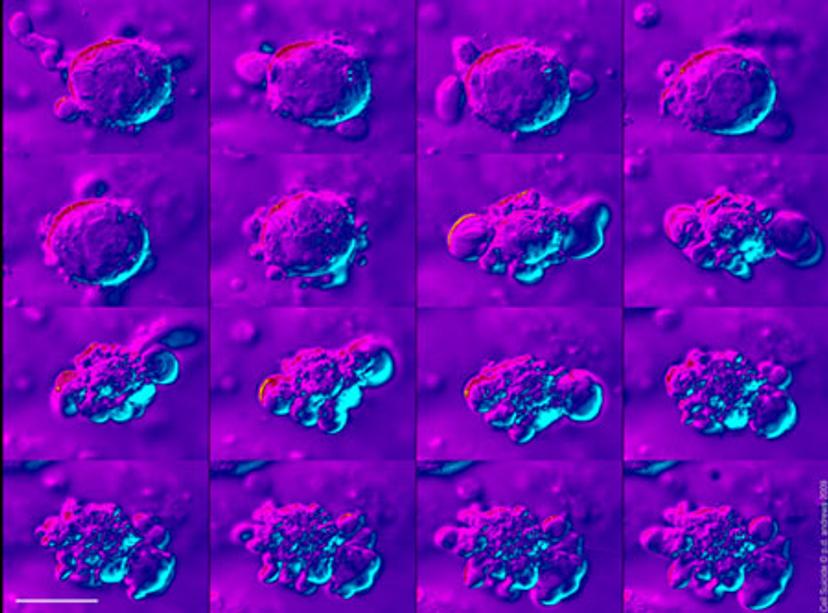

All these things will start to come together, and we’ll use multiple techniques going forward, especially when looking at large structures such as organoids or very small structures within the cell that might be dictating phenotypes.

The session that myself and Rob Vries of Hubrecht Organoid Technology have organized will cover the whole spectrum of cell-based assays relevant to disease, all the way from looking at cells to organoids.

We also have some talks from people working on the cutting-edge of organoid biology, not just in the characterization of them, but also in the application of organoids for predictive purposes such as drug discovery or patient stratification. Rob Vries and Bon-Kyoung Koo, of the Institute of Molecular Biotechnology (IMBA), Vienna and Florijn Dekkers of Princess Maximina Center for Pediatric Oncology, Utrecht, will talk about, various aspects of what they're doing in their own labs, some of which is advancing technologies to do with, for instance, CRISPR screening in tumor organoids or intestinal organoids and also using imaging technologies.